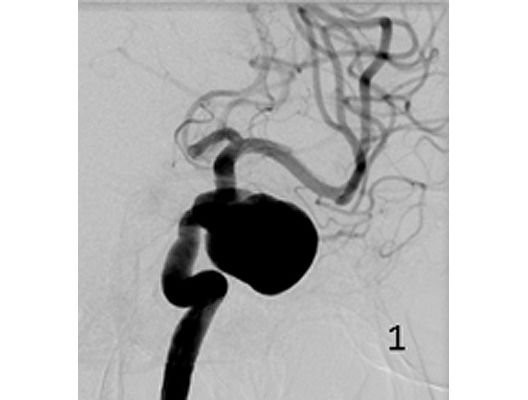

Mit den modernen Verfahren zur Wiedereröffnung von verschlossenen Blutgefäßen können wir Patienten mit Schlaganfall in vielen Fällen helfen. Das folgende Beispiel zeigt die angiographischen Bilder eines Patienten, der mit vollständiger Lähmung der rechten Körperhälfte und einer schweren Sprachstörung eingeliefert wurde. Ursächlich zeigte sich ein Verschluss der linken Halsschlagader, vermutlich auf dem Boden einer arteriosklerotischen Einengung (Bild 1). Das Gefäß wurde daraufhin mit einem Stent wiedereröffnet (Bild 2). Zusätzlich zeigte sich ein Verschluss der Endstrecke des Gefäßes durch Blutgerinnsel (Bild 3). Diese konnten vollständig entfernt werden (Bild 4). Der Patient erholte sich nach der Behandlung innerhalb weniger Tage vollständig.